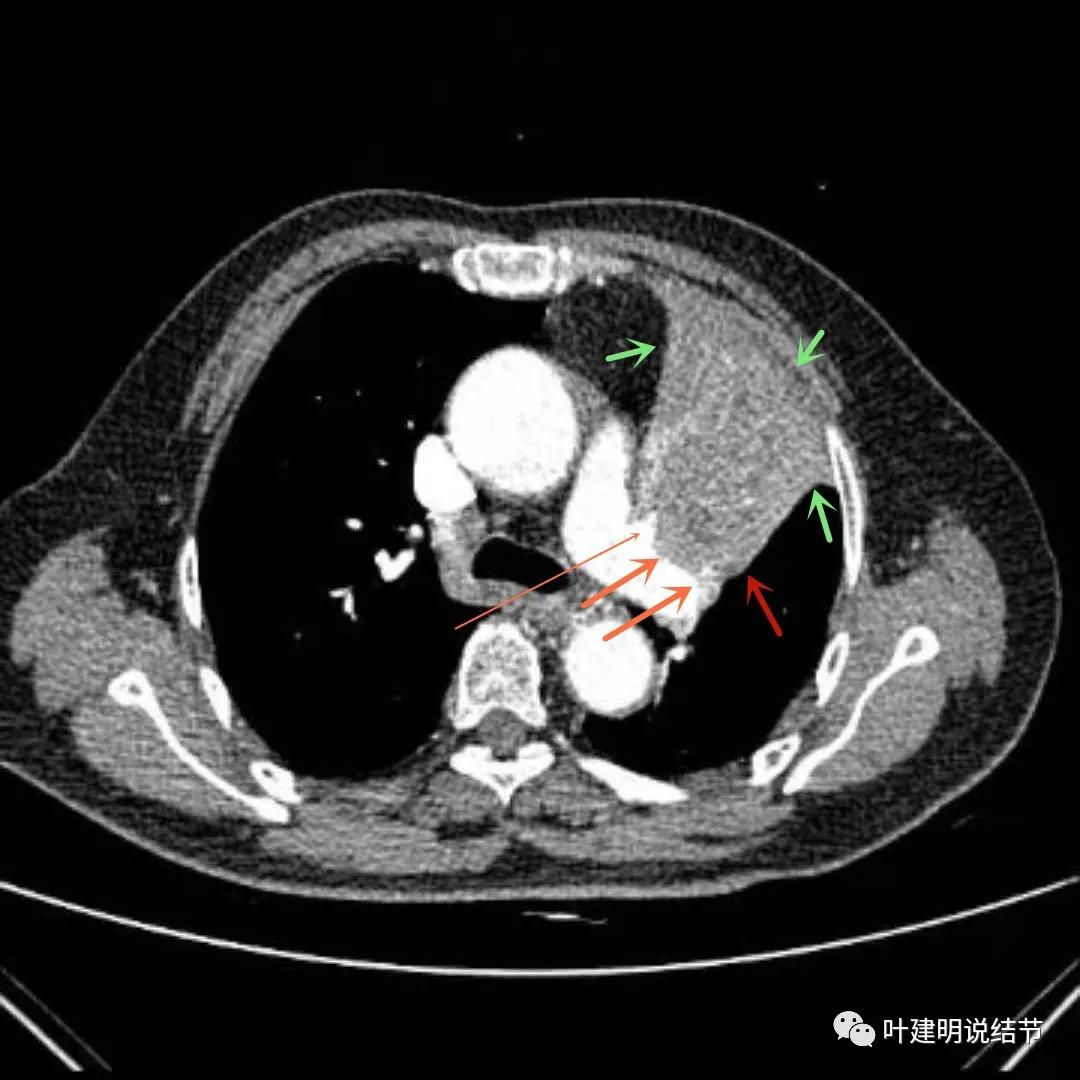

上图绿色箭头所指区域考虑为肺不张,红色示肿瘤处且有不均质与膨胀性,桔色箭头所指处显示肿瘤与肺动脉关系密切,考虑有侵犯肺动脉

上图绿色箭头所指区域考虑为肺不张,红色示肿瘤处且有不均质与膨胀性,桔色箭头所指处显示肿瘤与肺动脉关系密切,考虑有侵犯肺动脉。之所以肺动脉中间有软组织影,是因为肿瘤长到肺动脉与支气管之间的缝隙里,相当于血管是跨在肿瘤上,与肿瘤接触的这面是侵犯愈着的。